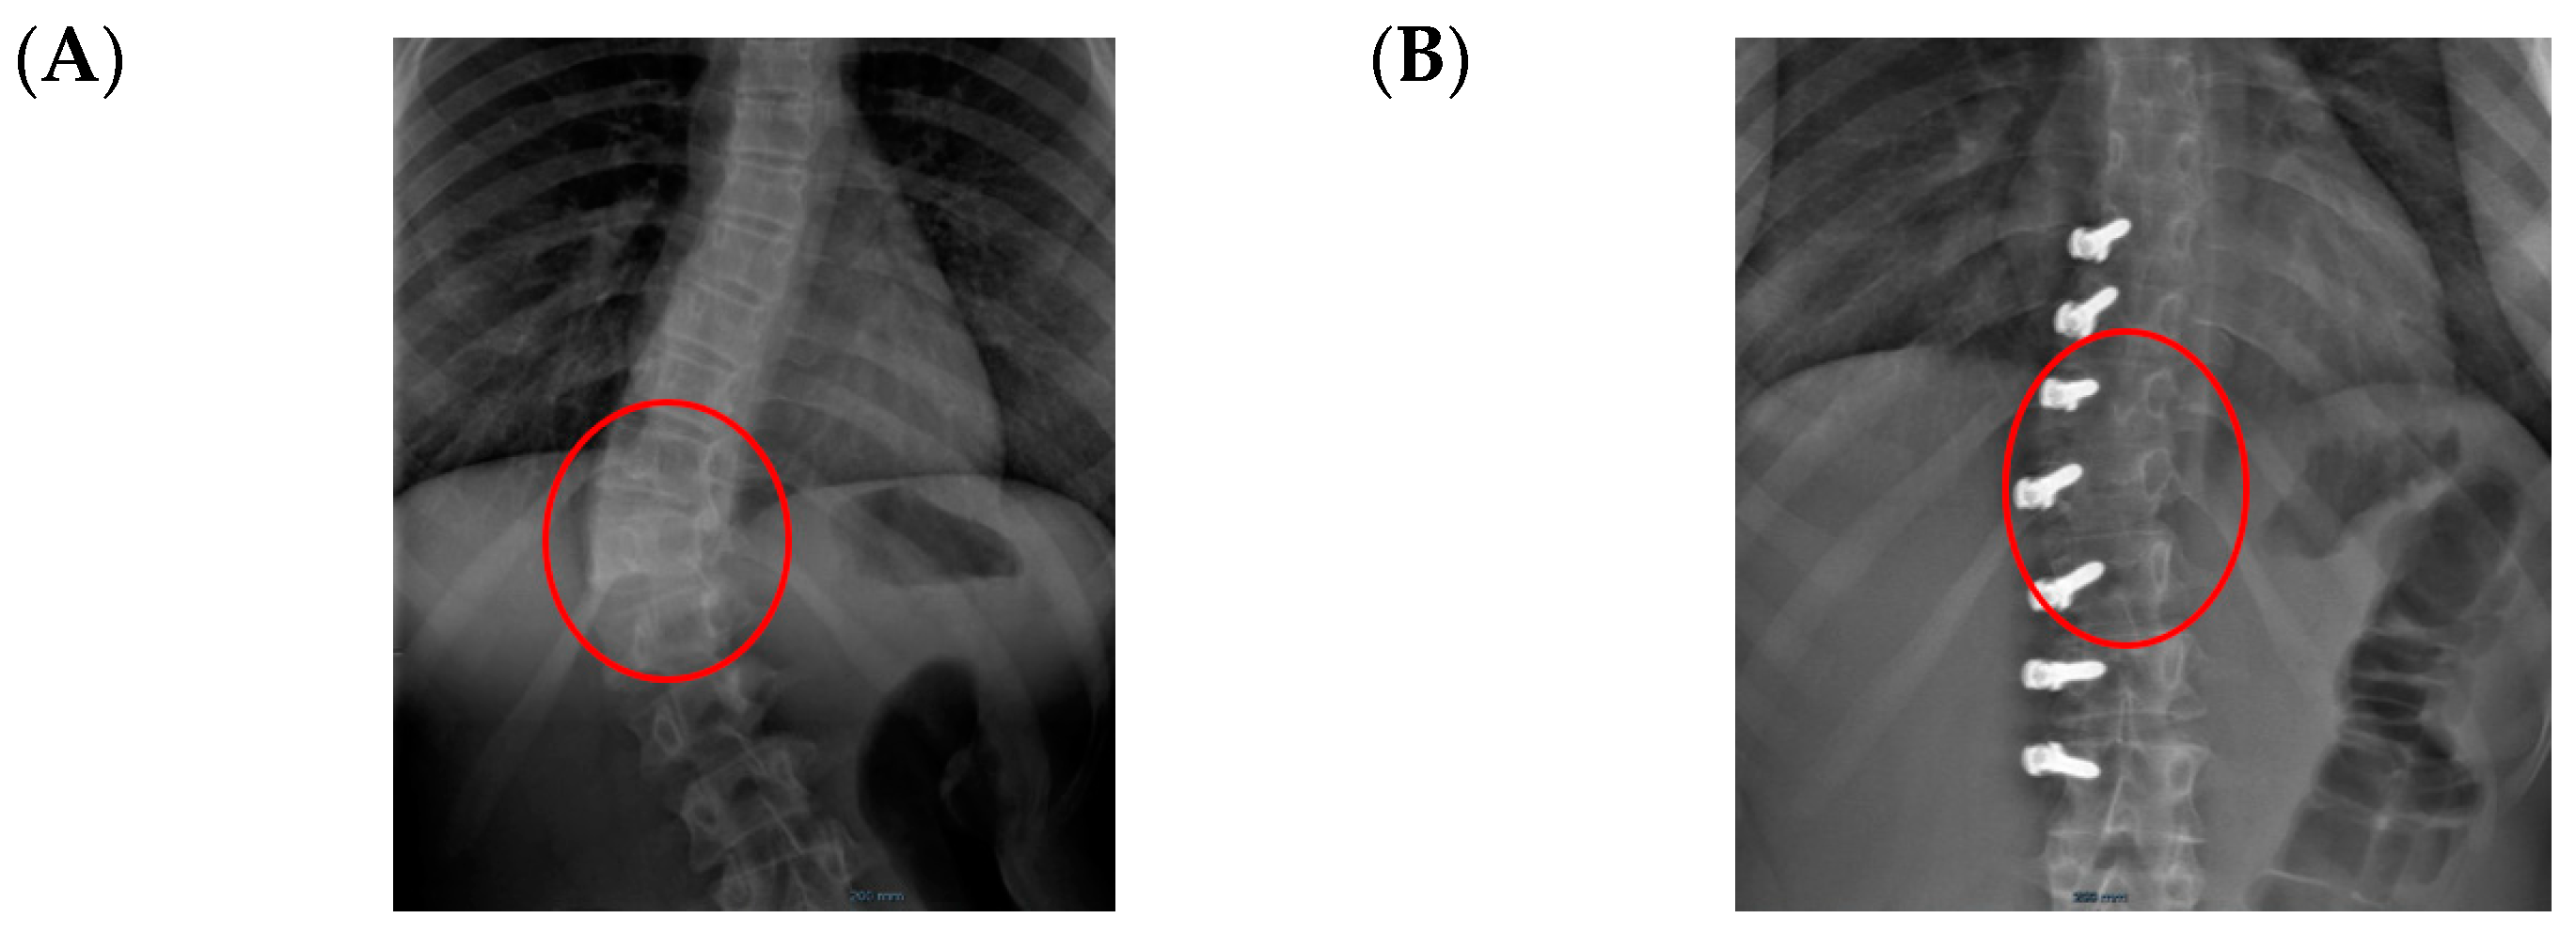

Concerning de-rotation, we can assess the apical vertebral rotation on the pre-operative radiograph as a Cobb grade +3 (Nash–Moe 50%) that improved to a Cobb grade +1 (Nash–Moe of 0%) in the last FU film (Figure 7) one year later.

Figure 7.

Apical improvement with progressive de-rotation of the vertebrae. (A) Pre-op. (B) FU at 1 year.